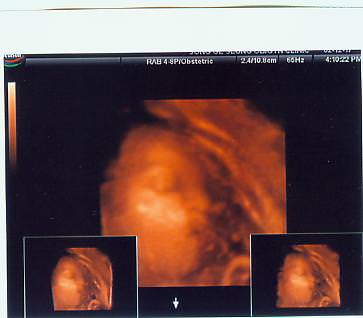

늠름하게 나온 하니군...^^